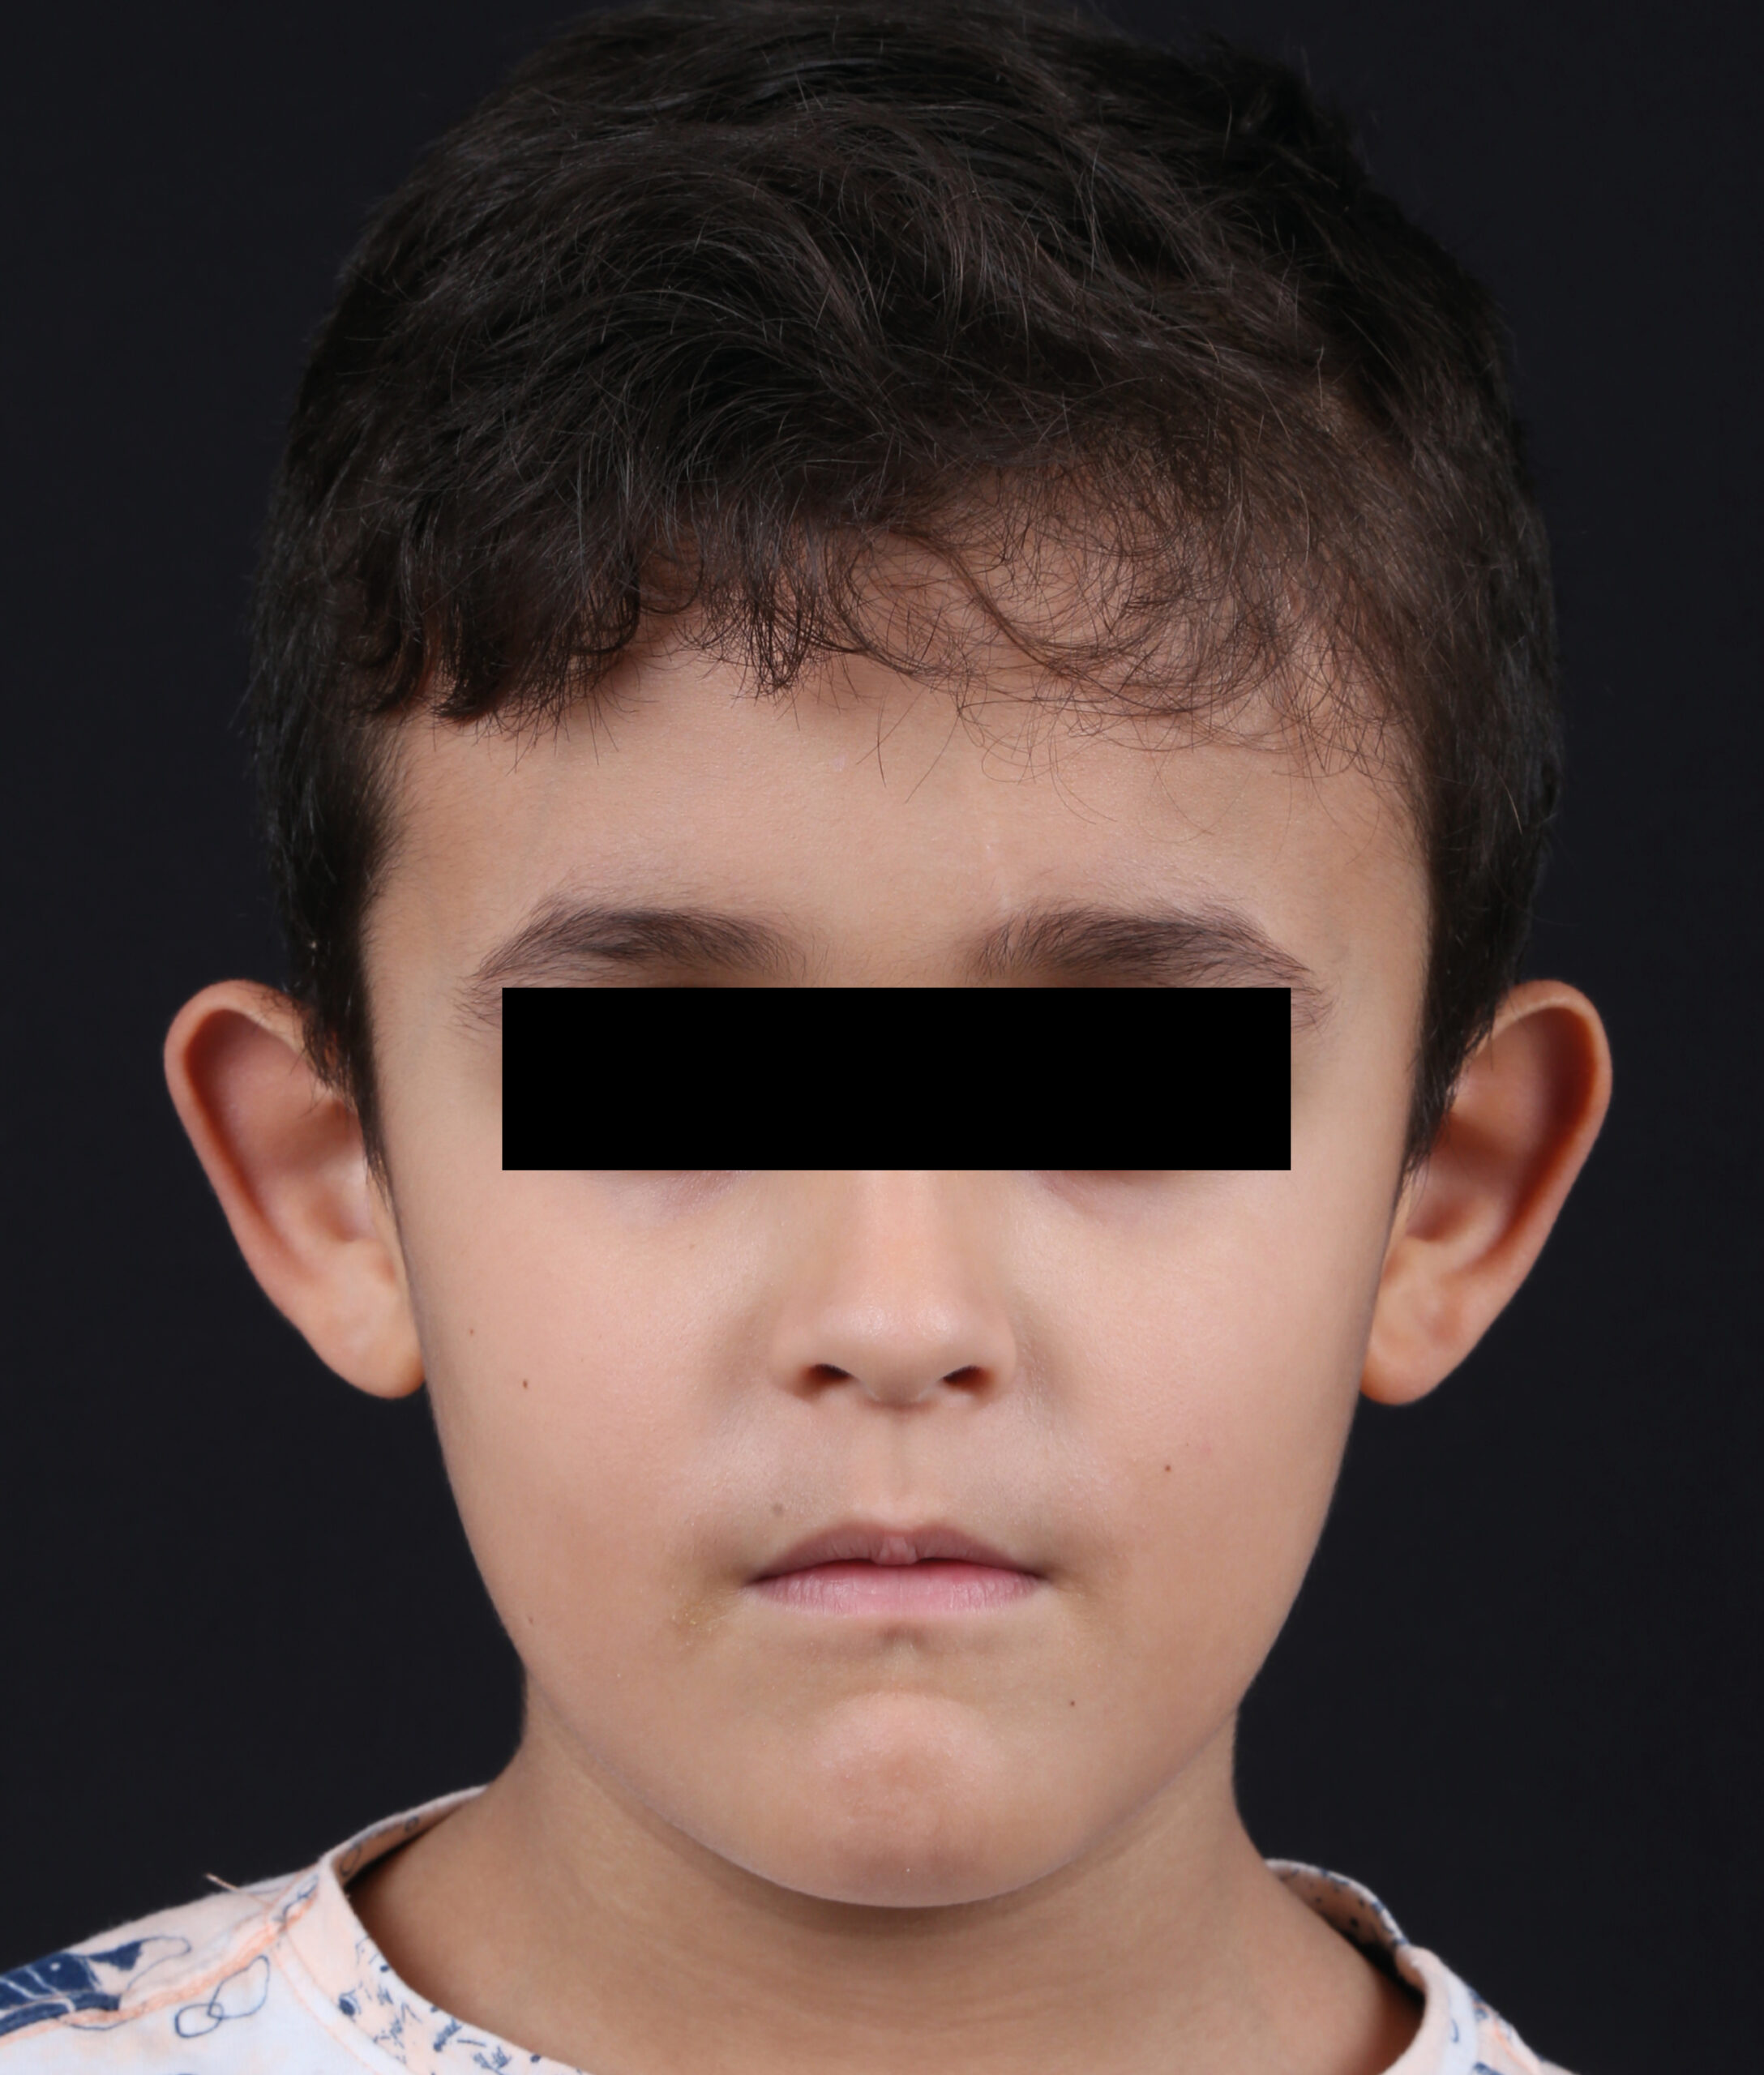

Fotografía Médica odontológica intra y extraoral

Registro fotográfico que se toma antes y después de los tratamientos odontológicos. sirve para evaluar y captar los rasgos intraorales y las características faciales.

Estas imágenes se emplean al iniciar el tratamiento mostrando el estado actual de la boca del paciente, se utilizan también para llevar un seguimiento y comparar luego del tratamiento para mostrar los resultados obtenidos.